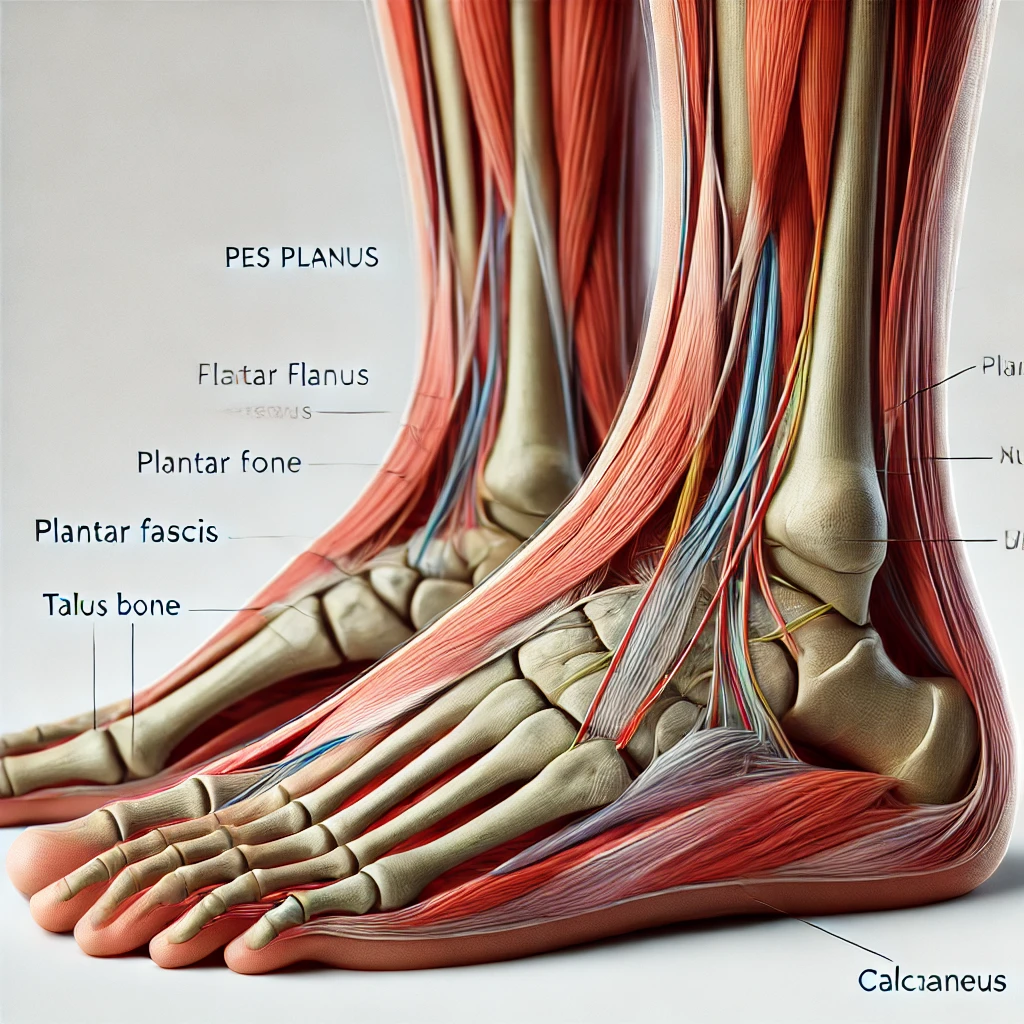

📋 목차아킬레스건염의 주요 원인아킬레스건염의 증상아킬레스건염의 진단 방법아킬레스건염의 치료법효과적인 스트레칭 방법아킬레스건염 예방 방법생활습관 개선 팁아킬레스건염 관련 자주 묻는 질문 FAQ아킬레스건염은 아킬레스건의 과도한 사용이나 부상으로 인해 발생하는 질환입니다. 반복적인 움직임, 부적절한 자세, 혹은 적절한 관리 부족으로 인해 쉽게 나타날 수 있습니다. 이를 효과적으로 관리하기 위해 증상의 원인을 파악하고 적절한 스트레칭과 생활습관 개선을 병행하는 것이 중요합니다. 아킬레스건염의 주요 원인아킬레스건염은 여러 요인으로 인해 발생할 수 있습니다. 반복적인 운동이나 과도한 훈련은 아킬레스건에 부담을 주어 염증을 유발할 수 있습니다. 특히 달리기나 점프 같은 고강도 운동이 큰 영향을 미칩니다. 또한, 평..